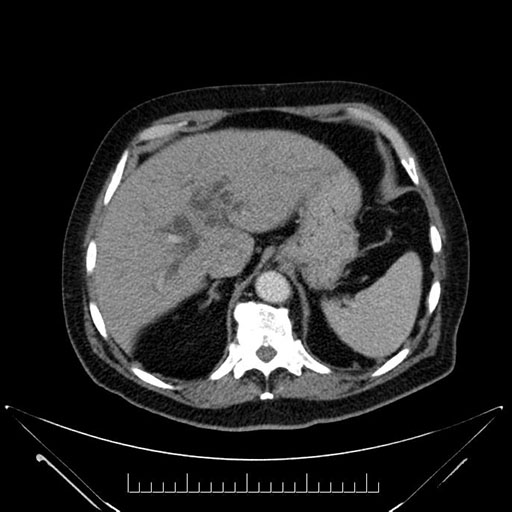

Whipple (pancreaticoduodenectomy) [case 7]

Imaging Analysis

Look through the patient's CT scan to identify any areas of concern for the necessary procedure.

Based on your CT findings, which issue(s) would give reason for "planned slowing down moment(s)" in this case?

Considering a standard Whipple procedure, what step(s) of the operation would you do differently in this case?